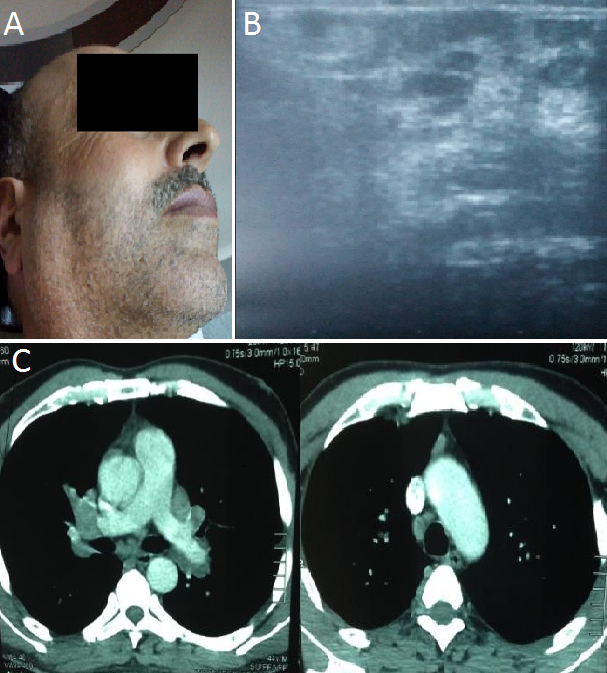

La sarcoïdose est une granulomatose systémique de cause inconnue, caractérisée par son polymorphisme clinique et une grande variété de ses modes de présentation. L'association de fièvre, d'uvéite, de parotidite et d'une paralysie faciale périphérique réalise le syndrome de Heerfordt qui présente une manifestation inhabituelle révélatrice de cette maladie. Nous rapportons le cas d'un patient de 46 ans qui présentait depuis trois mois une parotidomégalie bilatérale indolore et une fièvre (A). L'examen général était sans anomalies en particulier l'absence de paralysie faciale, la biologie était normale. L'échographie cervicale montrait une hypertrophie parotidienne bilatérale d'échostructure hétérogène multinodulaire en rapport avec des multiples images nodulaires hypoéchogènes de taille variable sans adénopathie cervicale (B) , l'examen ophtalmologique révélait une uvéite postérieure bilatérale associée à des nodules choroïdiens, la radiographie et le scanner thoracique révélaient des adénopathies médiastinales et une atteinte pulmonaire micronodulaire (C), l'intradermoréaction à la tuberculine était négative, le diagnostic de sarcoïdose était alors évoqué et confirmé par la biopsie des parotides, le patient a été mis sous corticothérapie par voie générale ce qui a permis la régression de la symptomatologie. Le syndrome de Heerfordt est une manifestation clinique inhabituelle (moins de 6%) au cours d'une sarcoïdose systémique, caractérisée par la triade parotidite, uvéite et paralysie faciale périphérique. Le traitement de choix est la corticothérapie par voie générale.